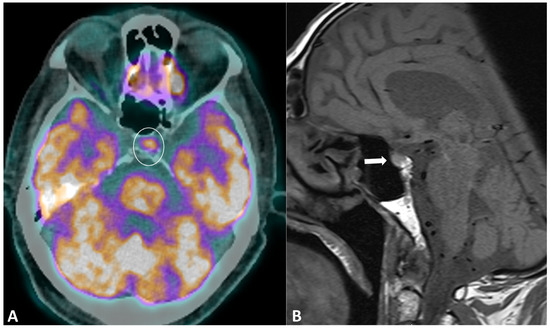

2.5.1. Ir-Hypophysitis

| Hypophysitis | CE brain MRI | Pituitary metastasis, adenoma | Diffuse and transient enlargement of the pituitary gland | |